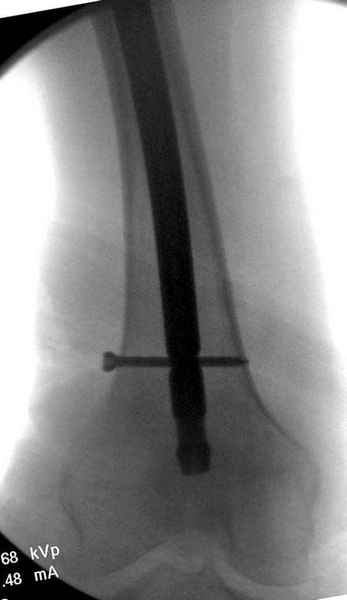

На второй день после выписки упал дома. Снимки приложены. Коллеги рекомендуют удаление шурупа и вытяжение. Что делать?

Правильно, ситуация изменилась, как говорят у нас теперь "different animal", надо решать проблему подвертельного перелома. При наличии различных вариантов фиксаторов, включая Страйкер Гамма 3, мы выбрали DePuy Antegrade Trachanteric Nail из-за многовариантности проксимальной фиксации и двойного изгиба. Вводится через вертел под 8 градусным углом, и есть достаточный передний диафизарный изгиб, предупреждающий пенетрацию дистального переднего кортекса.